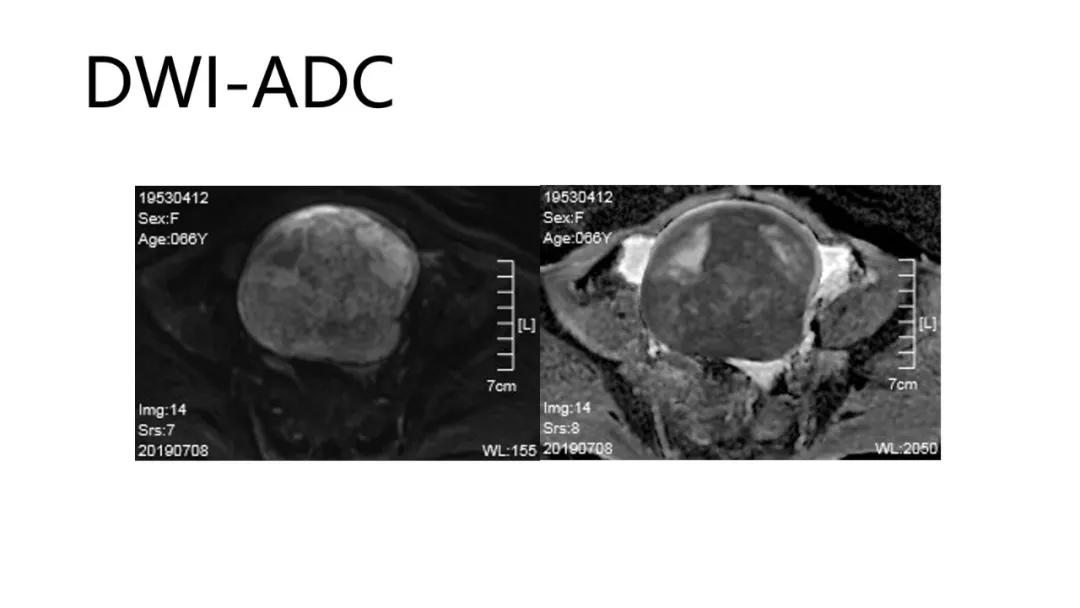

病变内出血病理血管~提示病变恶性

T2WI 低信号病灶:出血、平滑肌、纤维组织、卵巢甲状腺肿(凝胶)